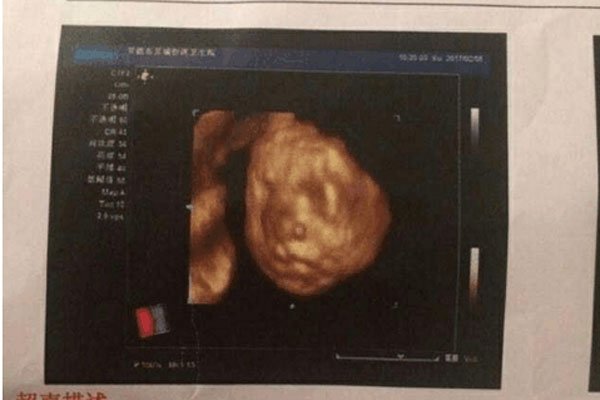

但是如果孕妇出血一直都是鲜红色的,那么一定要注意了,会发生这种情况一般是因为怀孕初期胚胎着床不稳定,出现这种情况并不代表是流产,只能说流产的几率比较大。第二种可能性是宫外孕,孕妇在6-7周时,用超声波还未看到胚胎,但是却有出血的症状,并且人类绒毛膜激素偏高时,这很可能就是宫外孕的情况,孕妈妈要注意伴随出血的同时是否有下腹疼痛的情况发生,有的话要立即就医。